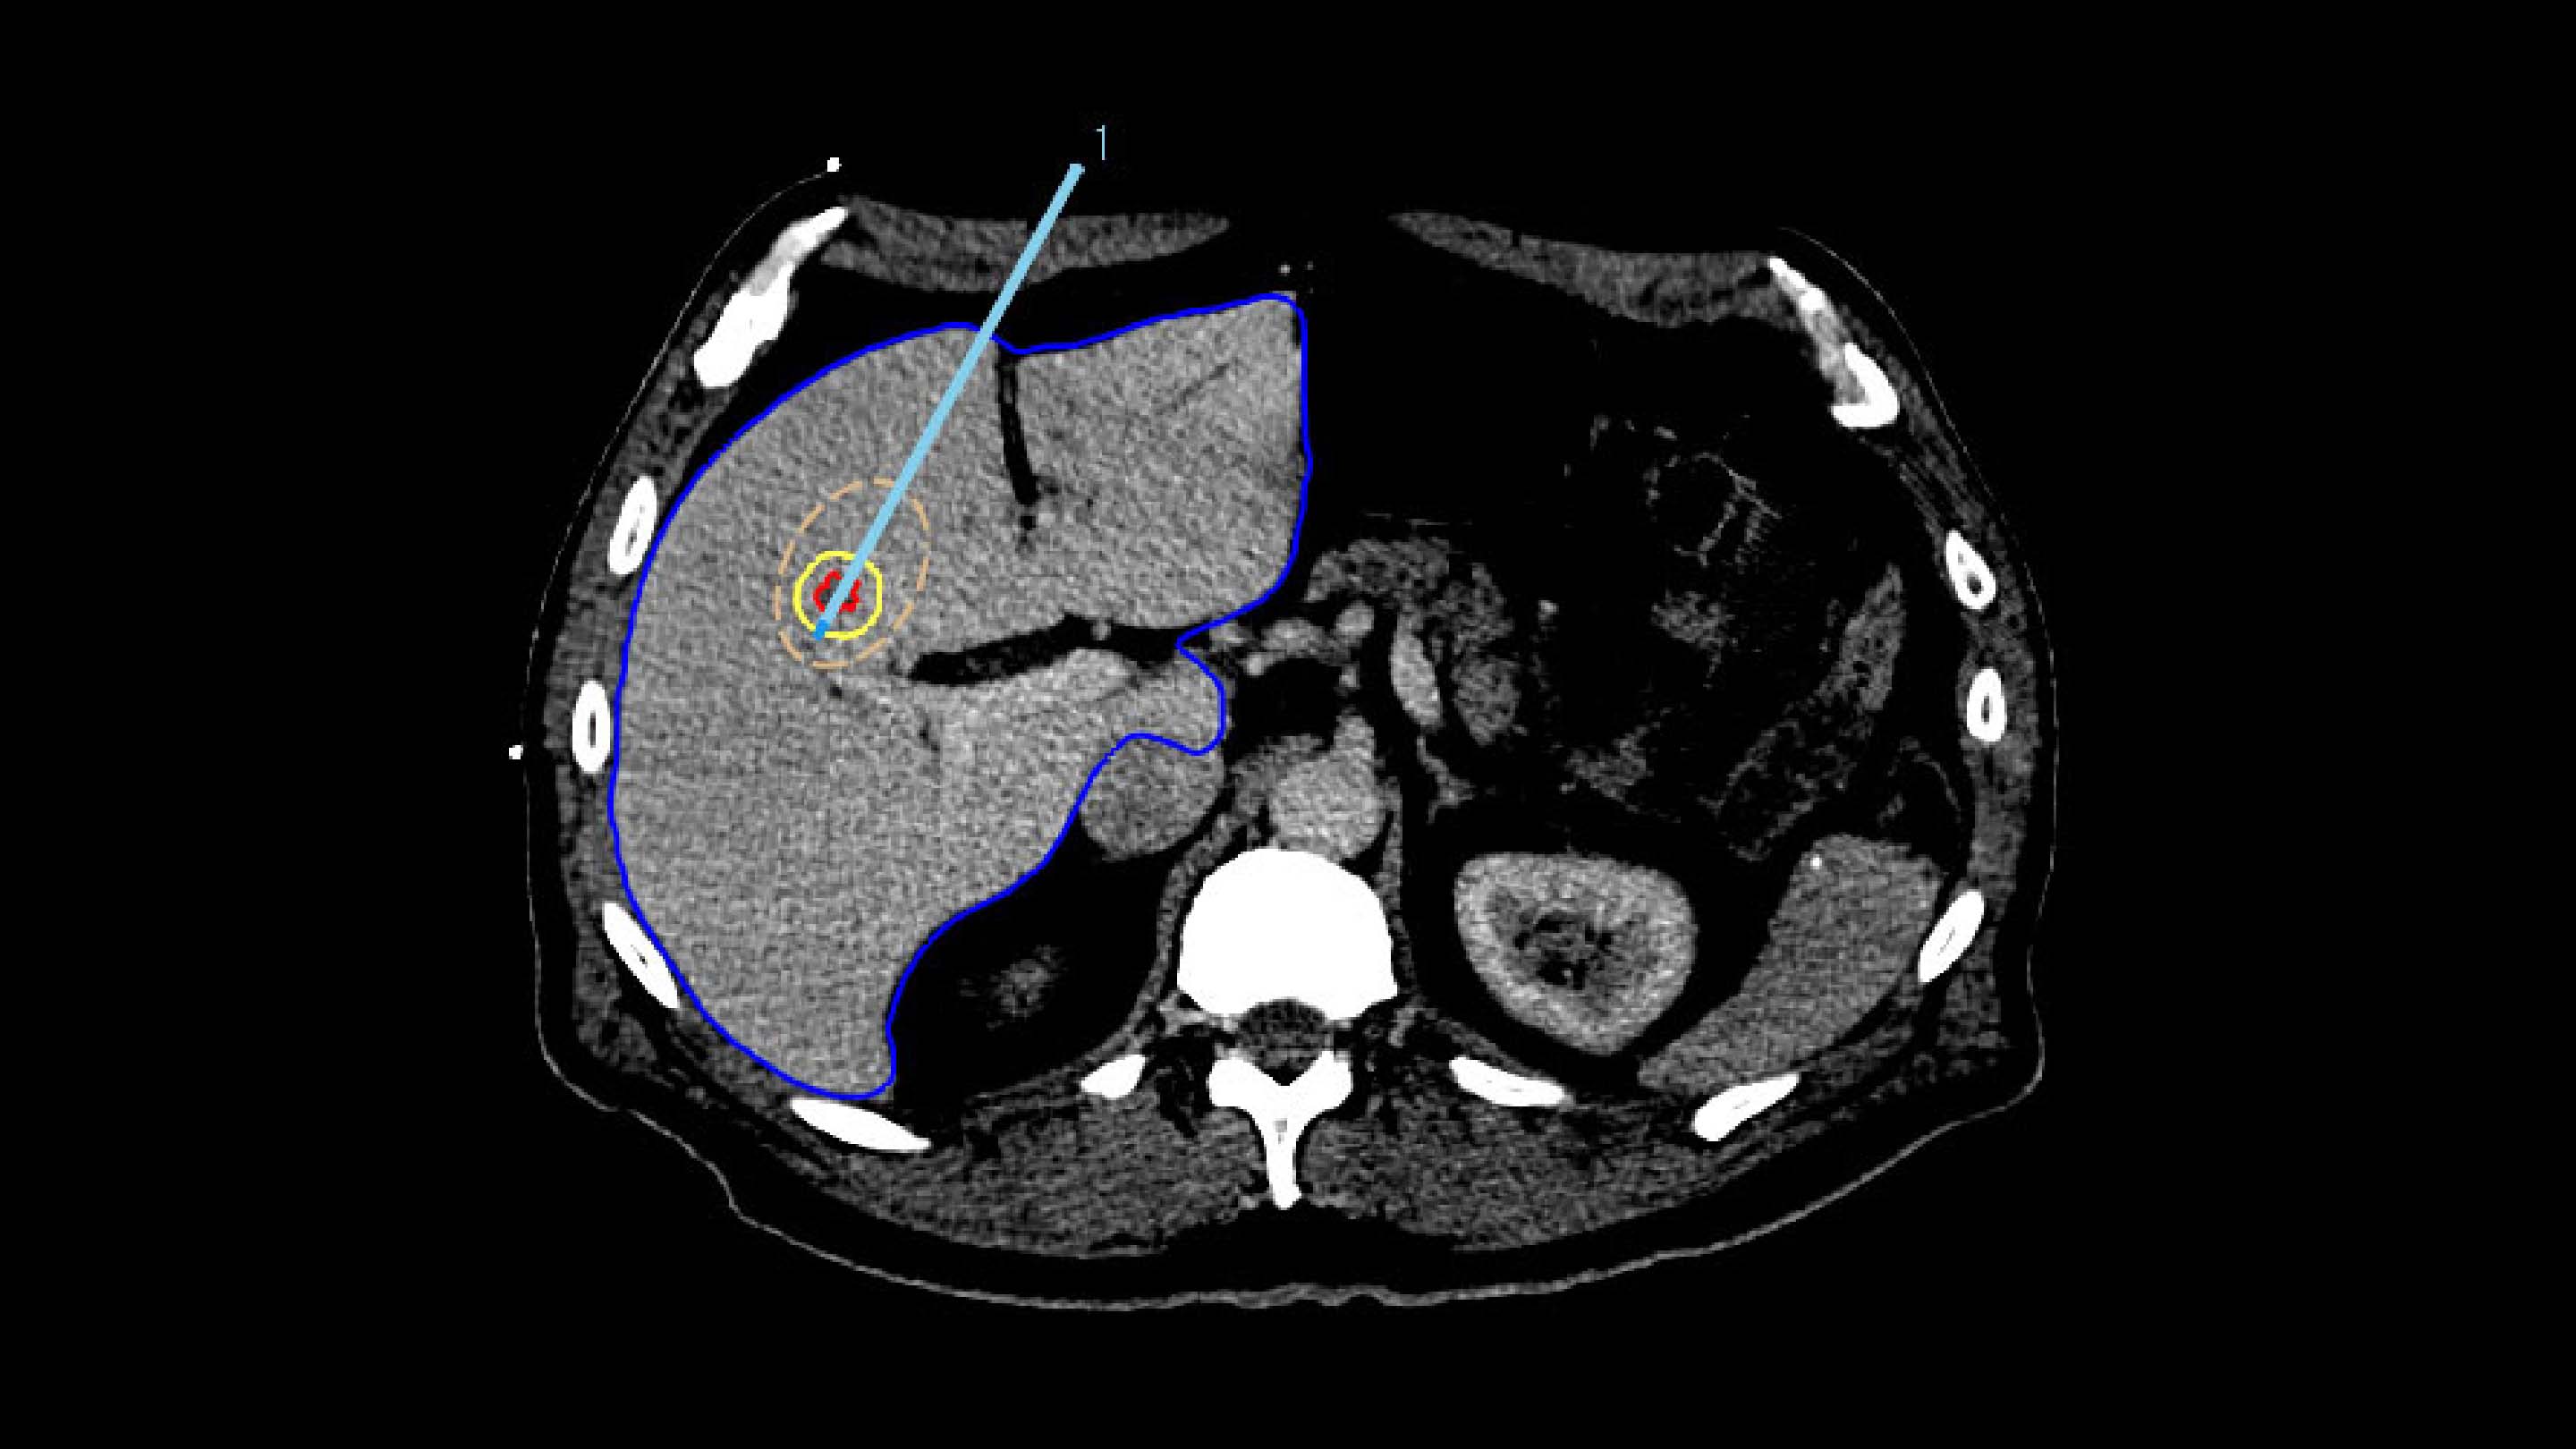

To ensure accurate applicator placement before treatment, the segmented tumors from the planning phase are mapped using deformable registration, allowing for a visualization of the anticipated tumor position. Additionally, the ablation zone can be estimated based on the applicator parameters, such as its current position, selected power, and ablation duration.